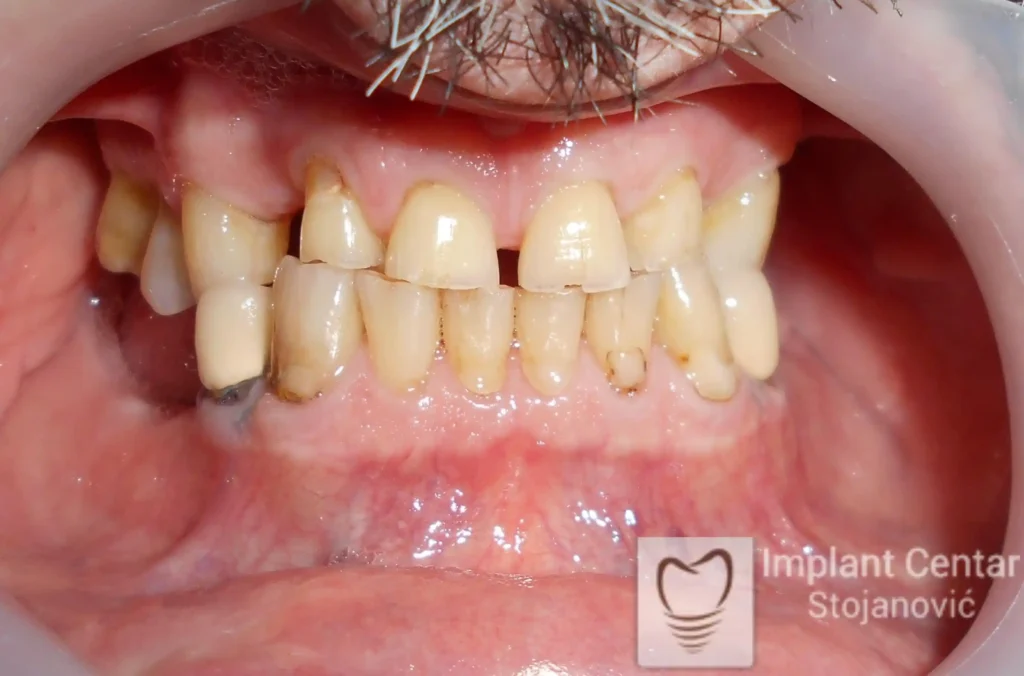

Pacijent sa rascepom usne, nepca i alveolarnog grebena uspešno je rehabilitovan fiksnim protetskim radom na implantatima. Pre dolaska u našu ordinaciju, pacijent je u gornjoj vilici nosio totalnu protezu preko preostalih zuba, dok je u donjoj vilici bio zbrinut parcijalnom mobilnom protezom. Tokom višegodišnje potrage za adekvatnim rešenjem, pacijent nije uspeo da pronađe zadovoljavajuću terapijsku opciju ni u zemlji ni u inostranstvu.

Nakon detaljnog kliničkog pregleda i analize radioloških snimaka, izrađen je sveobuhvatan plan terapije sa ciljem uklanjanja mobilnih proteza i postizanja maksimalne funkcionalne i estetske rehabilitacije. Zbog loše biološke vrednosti preostalih zuba, doneta je odluka o njihovom vađenju i ugradnji dentalnih implantata.

Poseban terapijski izazov predstavljalo je premošćavanje defekta nastalog usled rascepa, kao i ograničena količina raspoložive kosti u gornjoj vilici. Primenom većeg broja implantata i odgovarajućih procedura nadoknade kosti, postignuta je stabilna osnova za fiksni protetski rad.

Tokom perioda oseointegracije, pacijent je bio zbrinut fiksnim privremenim krunicama, čime je već pet dana nakon intervencije obezbeđena potpuna funkcionalna i estetska rehabilitacija. Nakon završetka perioda integracije implantata, izrađeni su definitivni cirkonijum-keramički mostovi na implantatima.

Pacijent je izuzetno zadovoljan postignutim rezultatom, navodeći da po prvi put jasno oseća svoje nepce tokom žvakanja, kao i da se smeje sa punim samopouzdanjem.